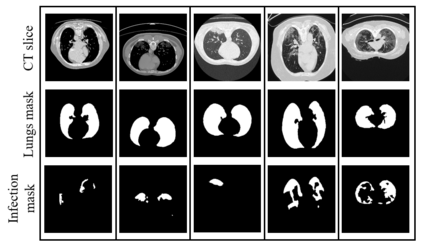

The pandemic of novel severe acute respiratory syndrome coronavirus 2 (SARS-CoV-2) also known as COVID-19 has been spreading worldwide, causing rampant loss of lives. Medical imaging such as computed tomography (CT), X-ray, etc., plays a significant role in diagnosing the patients by presenting the excellent details about the structure of the organs. However, for any radiologist analyzing such scans is a tedious and time-consuming task. The emerging deep learning technologies have displayed its strength in analyzing such scans to aid in the faster diagnosis of the diseases and viruses such as COVID-19. In the present article, an automated deep learning based model, COVID-19 hierarchical segmentation network (CHS-Net) is proposed that functions as a semantic hierarchical segmenter to identify the COVID-19 infected regions from lungs contour via CT medical imaging. The CHS-Net is developed with the two cascaded residual attention inception U-Net (RAIU-Net) models where first generates lungs contour maps and second generates COVID-19 infected regions. RAIU-Net comprises of a residual inception U-Net model with spectral spatial and depth attention network (SSD), consisting of contraction and expansion phases of depthwise separable convolutions and hybrid pooling (max and spectral pooling) to efficiently encode and decode the semantic and varying resolution information. The CHS-Net is trained with the segmentation loss function that is the weighted average of binary cross entropy loss and dice loss to penalize false negative and false positive predictions. The approach is compared with the recently proposed research works on the basis of standard metrics. With extensive trials, it is observed that the proposed approach outperformed the recently proposed approaches and effectively segments the COVID-19 infected regions in the lungs.